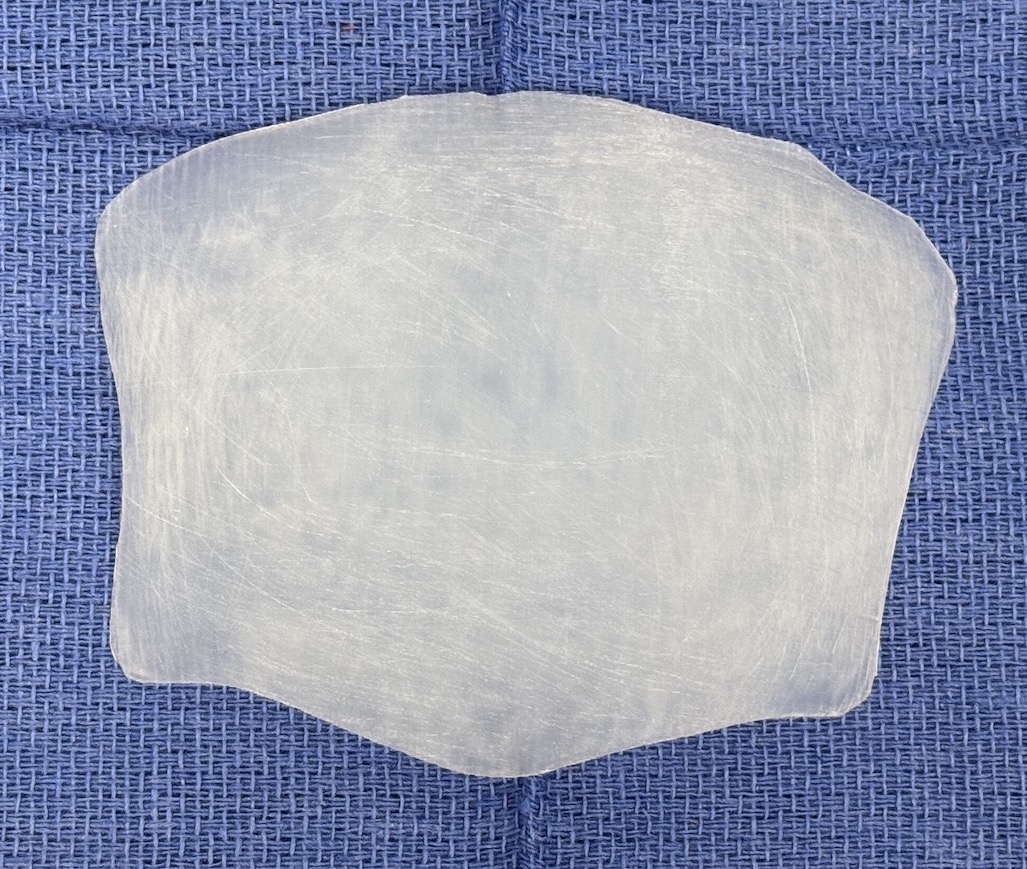

Desire for augmentation of flat back of the head that developed after wide excision and skin grafting of chronic scalp skin infections. This actually represented a loss of scalp thickness rather than a bone deficiency.

Occipital skull augmentation using a custom made implant designed from a measured template overlay on the depressed scalp area. Technically this was a 'scalp augmentation' using a bone-based implant.

Desire for augmentation of flat back of the head that developed after wide excision and skin grafting of chronic scalp skin infections. This actually represented a loss of scalp thickness rather than a bone deficiency.

Occipital skull augmentation using a custom made implant designed from a measured template overlay on the depressed scalp area. Technically this was a 'scalp augmentation' using a bone-based implant.